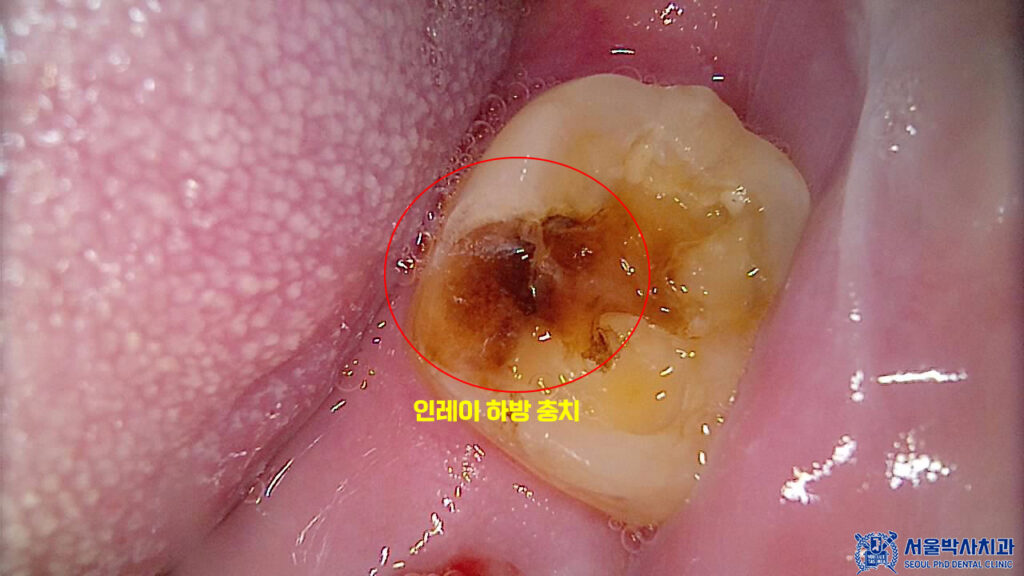

이후 임플란트를 진행한 뒤 치아는

타 치과에서 금 인레이를 진행하셨었으나

씹을 때 통증이 심한 치아 중 하나였으며,

인레이 하방으로 충치가 생겨있었습니다.

본원은 자연치아 살리기를

중요시하고 있기 때문에

임플란트를 진행하지 않고

살릴 수 있는 가능성을 되돌아보며

신경치료를 진행하여

치아를 살려보기로 하였습니다.